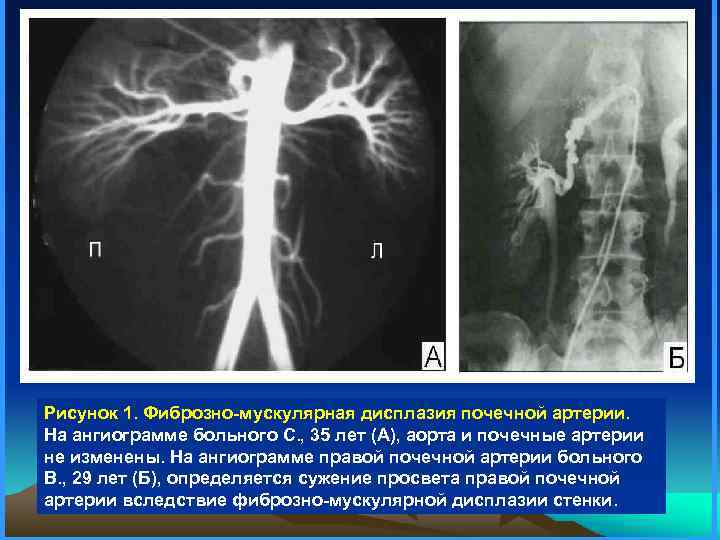

Рисунок 1. Фиброзно-мускулярная дисплазия почечной артерии. На ангиограмме больного С. , 35 лет (А), аорта и почечные артерии не изменены. На ангиограмме правой почечной артерии больного В. , 29 лет (Б), определяется сужение просвета правой почечной артерии вследствие фиброзно-мускулярной дисплазии стенки.

Рисунок 1. Фиброзно-мускулярная дисплазия почечной артерии. На ангиограмме больного С. , 35 лет (А), аорта и почечные артерии не изменены. На ангиограмме правой почечной артерии больного В. , 29 лет (Б), определяется сужение просвета правой почечной артерии вследствие фиброзно-мускулярной дисплазии стенки.